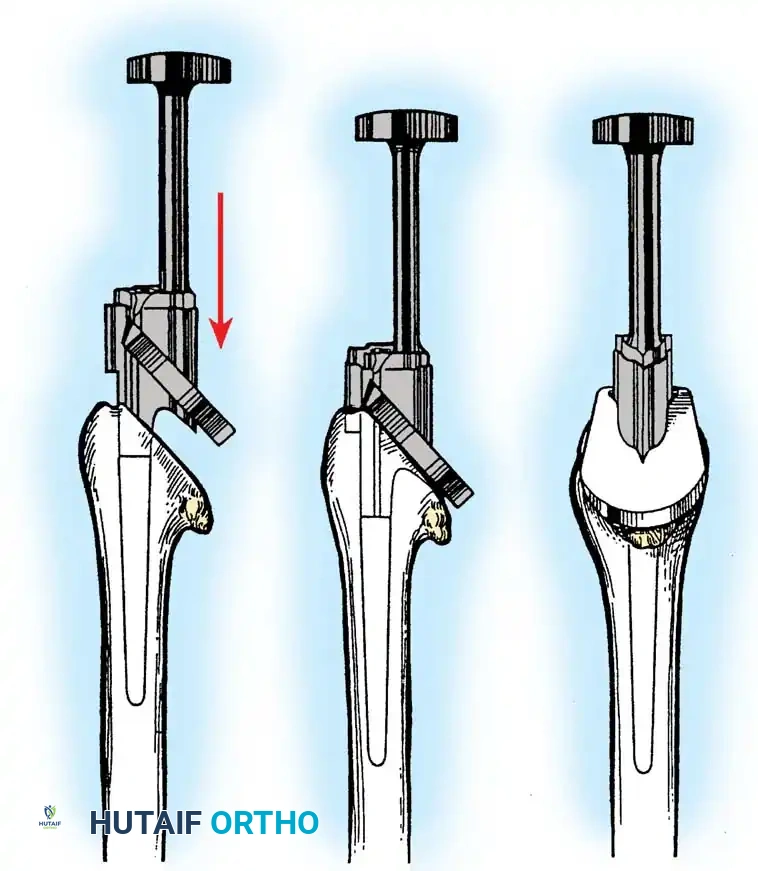

3. Canal Preparation and Implantation

The humeral and ulnar canals are sequentially broached.

- A cement restrictor is placed in both canals.

- Antibiotic-loaded polymethylmethacrylate (PMMA) bone cement is injected in a retrograde fashion.

- The components are inserted, and the articulation is linked using the manufacturer-specific locking pin mechanism.

Surgical Warning: The ulnar component must be inserted with precise rotational alignment. Malrotation will lead to eccentric wear of the polyethylene bushings and early catastrophic failure of the linkage mechanism.